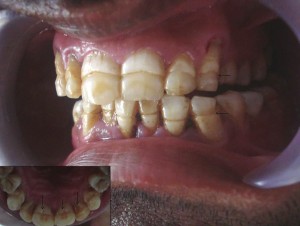

Системная неспецифическая гипоплазия тканей зуба. Порок развития, проявляющийся в нарушении строения и минерализации тканей зуба, возникающий как результат влияния различных факторов на зачаток в период формирования и обызвествления зуба. Это воздействие приводит к нарушению эмбриогенеза зуба, что проявляется неспецифическим (однотипным) нарушением процесса формирования структур и минерализации тканей зуба.

Различают гипоплазию системную и очаговую. Системной гипоплазией считается нарушение строения тканей всех зубов или группы зубов, формирующихся в один и тот же промежуток времени. Очаговая гипоплазия характеризуется пороком развития тканей одного или нескольких зубов, формировавшихся в очаге воспаления окружающих фолликул тканей, в зоне опухолевого роста или подвергшихся травме.

Клиническая картина. Системная неспецифическая гипоплазия молочных зубов преимущественно возникает и формируется под влиянием неблагоприятных факторов в антенатальном периоде. Каждому сроку антенатального периода соответствует определенная степень формирования и минерализации различных групп временных зубов.